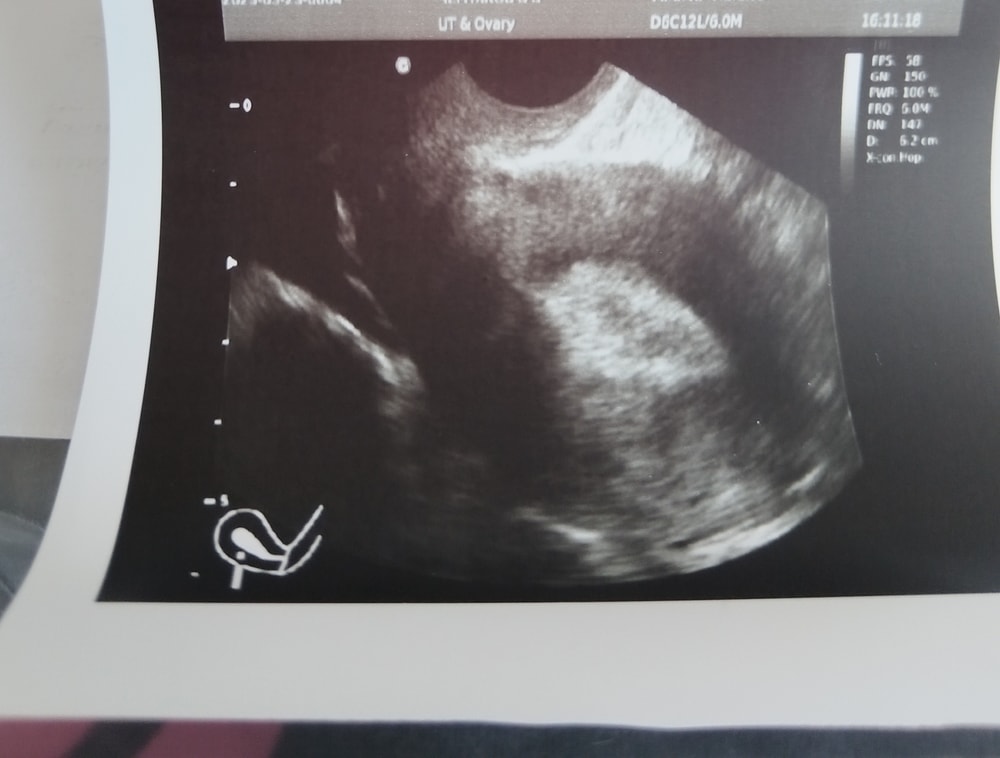

Кто разбирается в узи

Хороший фоллик, явно больше заключения. Думаю завтра - послезавтра О

Как то странно он фолликул измерял🤔. У меня двойная была, по этому указано 2 размера. А у вас он и вдоль и поперёк зачем-то измерил... Но судя по его записям доминантный фолликул у Вас 18,3 мм, овуляция может быть от 19 мм, т.е. начиная с сегодняшнего дня и ближайшие 2-3 дня. У всех организмы разные, по этому точно сказать нельзя когда будет овуляция. Фолликул в день прибавляет от 1 до 2 мм. Изображение